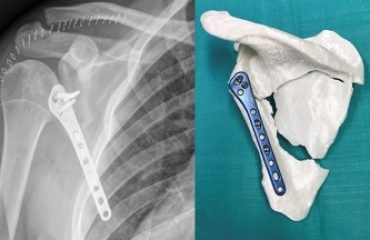

- 3 ORDEN. Siempre debe hacerse la reconstrucción en el siguiente orden: hueso, tendón, arteria, vena y nervio.

El equipo de rehabilitación ha iniciado la terapia con el paciente, que ya moviliza activamente las articulaciones metacarpofalángicas. Tras comprobar la consolidación de las fracturas, se retirarán las agujas que fijan las articulaciones interfalángicas en extensión, e iniciará los ejercicios de flexo-extensión de los dedos.

En este caso, se estima que el paciente pueda hacer pinza dentro de un mes, en dos meses podría agarrar objetos y una vez transcurridos seis meses de rehabilitación podría haberse alcanzado una funcionalidad casi total.